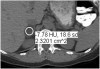

Quantitative imaging (QI) is increasingly applied in modern radiology practice, assisting in the clinical assessment of many patients and providing a source of biomarkers for a spectrum of diseases. QI is commonly used to inform patient diagnosis or prognosis, determine the choice of therapy, or monitor therapy response. Because most radiologists will likely implement some QI tools to meet the patient care needs of their referring clinicians, it is important for all radiologists to become familiar with the strengths and limitations of QI. The Association of University Radiologists Radiology Research Alliance Quantitative Imaging Task Force has explored the clinical application of QI and summarizes its work in this review. We provide an overview of the clinical use of QI by discussing QI tools that are currently used in clinical practice, clinical applications of these tools, approaches to reporting of QI, and challenges to implementing QI. It is hoped that these insights will help radiologists recognize the tangible benefits of QI to their patients, their referring clinicians, and their own radiology practice.